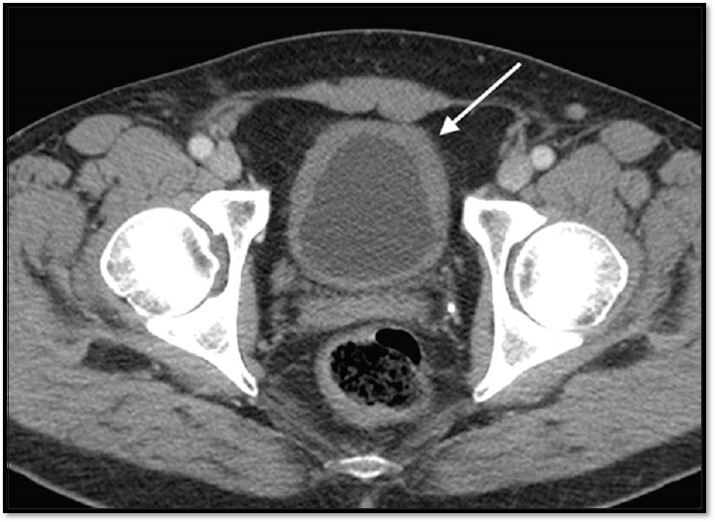

4

Q

What pathology is seen here?

A

Unilateral Renal Agenesis